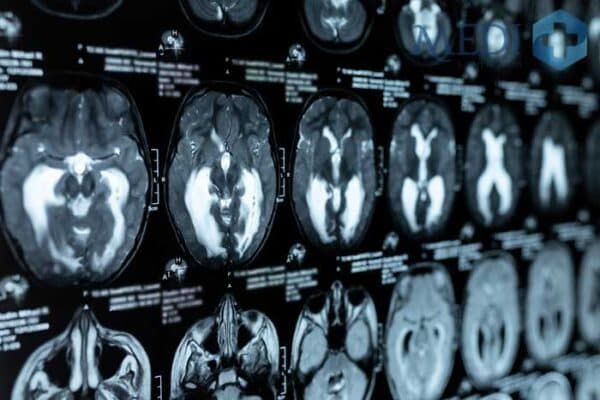

– Chụp sọ não

– Nghi ngờ về bệnh u não, u thần kinh sọ não, tai biến, gặp chấn thương, động kinh, bệnh chất trắng, bệnh viêm não, viêm màng não, các dị tật bẩm sinh hoặc các bệnh liên quan mạch máu,…

Hình ảnh chụp MRI có giá trị cao giúp bác sĩ chẩn đoán chính xác bệnh lý gặp phải.